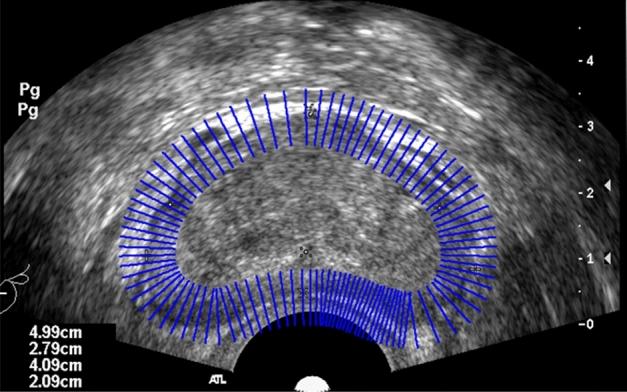

一种语义约束下的前列腺超声图像双向分割方法。

A bi-directional segmentation method for prostate ultrasound images under semantic constraints.

Due to the lack of sufficient labeled data for the prostate and the extensive and complex semantic information in ultrasound images, accurately and quickly segmenting the prostate in transrectal ultrasound (TRUS) images remains a challenging task. In this context, this paper proposes a solution for TRUS image segmentation using an end-to-end bidirectional semantic constraint method, namely the BiSeC model. The experimental results show that compared with classic or popular deep learning methods, this method has better segmentation performance, with the Dice Similarity Coefficient (DSC) of 96.74% and the Intersection over Union (IoU) of 93.71%. Our model achieves a good balance between actual boundaries and noise areas, reducing costs while ensuring the accuracy and speed of segmentation.

摘要

由于前列腺缺乏足够的标注数据,且超声图像中的语义信息广泛而复杂,在经直肠超声(TRUS)图像中准确、快速地分割前列腺仍然是一项具有挑战性的任务。在此背景下,本文提出了一种使用端到端双向语义约束方法的TRUS图像分割解决方案,即BiSeC模型。实验结果表明,与经典或流行的深度学习方法相比,该方法具有更好的分割性能,骰子相似系数(DSC)为96.74%,交并比(IoU)为93.71%。我们的模型在实际边界和噪声区域之间实现了良好的平衡,在确保分割准确性和速度的同时降低了成本。